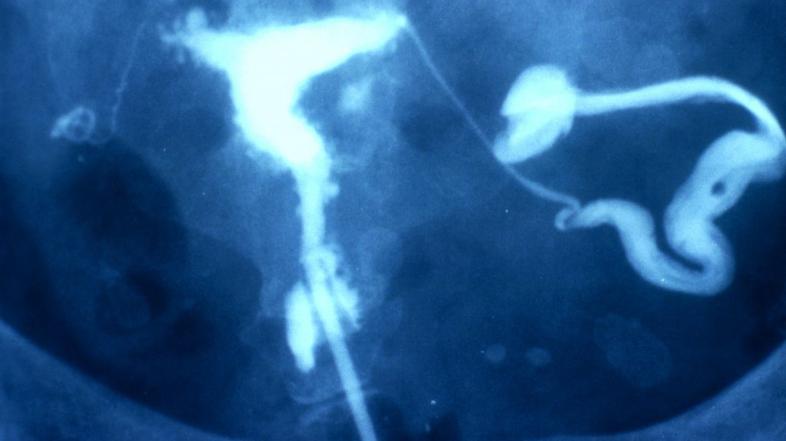

Prvi opis endometrioze in tudi prvo operacijo zaradi endometrioze ciste v jajčniku je leta 1998 objavil Thomas Cullen. Intenzivnejše raziskovanje endometrioze je začel John Sampson, ki se je vse pogosteje srečeval s pacijentkami s težavami zaradi endometrioze in je leta 1921 postavil prvo teorijo o nastanku endometrioze. Sicer se je pomemben napredek v raziskovanju začel z uvedbo laparoskopije in laparoskopske kirurgije v začetku šestdesetih let. Strokovnjaki so prišli do spoznanja, da ne gre za enotno bolezen, temveč da obstajajo tri različne oblike endometrioze: peritonealna (zasevki maternične sluznice po potrebušnici), endometrioza jajčnika (t.i. čokoladne ciste) in globoka infiltrativna endometrioza (prizadene globlje plasti male medenice in tudi sosednje organe: črevo, mehur, sečevode). Omenjene tri oblike se razlikujejo po načinu nastanka in je tudi njihovo delovanje različno (razlikujejo se po patofiziologiji kot to strokovno imenjujemo).

Diagnostični postopki so potrebni, in sicer posvet pri ginekologu, ginekološki pregled, ultrazvok, kar pa je mnogokrat za deklice in mladostnice zelo stresno. Endometriozo zaenkrat lahko dokončno potrdimo in kirurško odstranimo zgolj z laparoskopijo, ki pa je invaziven kirurški postopek in zanj se odločimo po tehtnem premisleku, na osnovi suma na endometriozo in ob hudih težavah. Vsekakor pa mora poseg narediti ginekolog z izkušnjami o kirurškem zdravljenju endometrioze. Nepopolna odstranitev vseh sprememb vodi v ponovne in ponovne operacije. Če se dekleta ali starši ne odločijo za kirurško zdravljenje je možna tudi diagnostika z magnetno resonance ter določitev tumorskega označevalca Ca-125 v krvi.